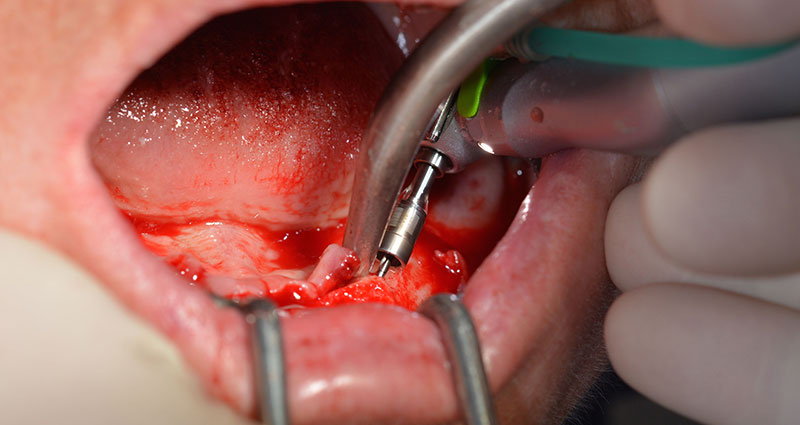

After removal of the residual dentition in the mandible, the alveolar crest was exposed from 37 to 47.

The mental foramen was first identified as a limiting anatomical structure and then the cortical bone of the crest was smoothed with the straight handpiece and a large rose-head bur (Fig. 4).